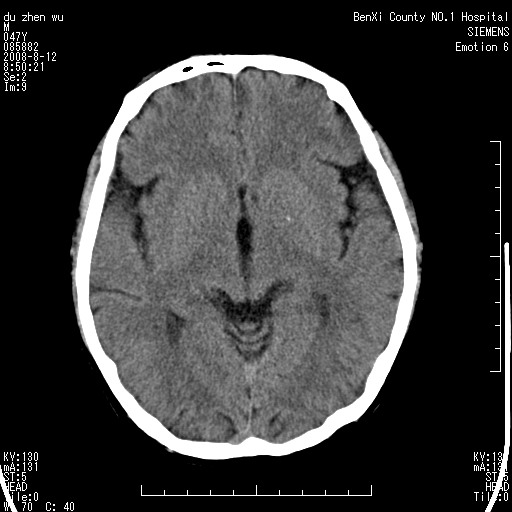

标题: CT15142:M47Y,胼胝体低密度病变 [打印本页]

标题: CT15142:M47Y,胼胝体低密度病变

男、时有神智不清,头晕,能正常回答问题,无肢体偏瘫

考虑胼胝体变性(脱髓鞘病变),找到一篇论文

典型,支持 胼胝体变性(脱髓鞘病变